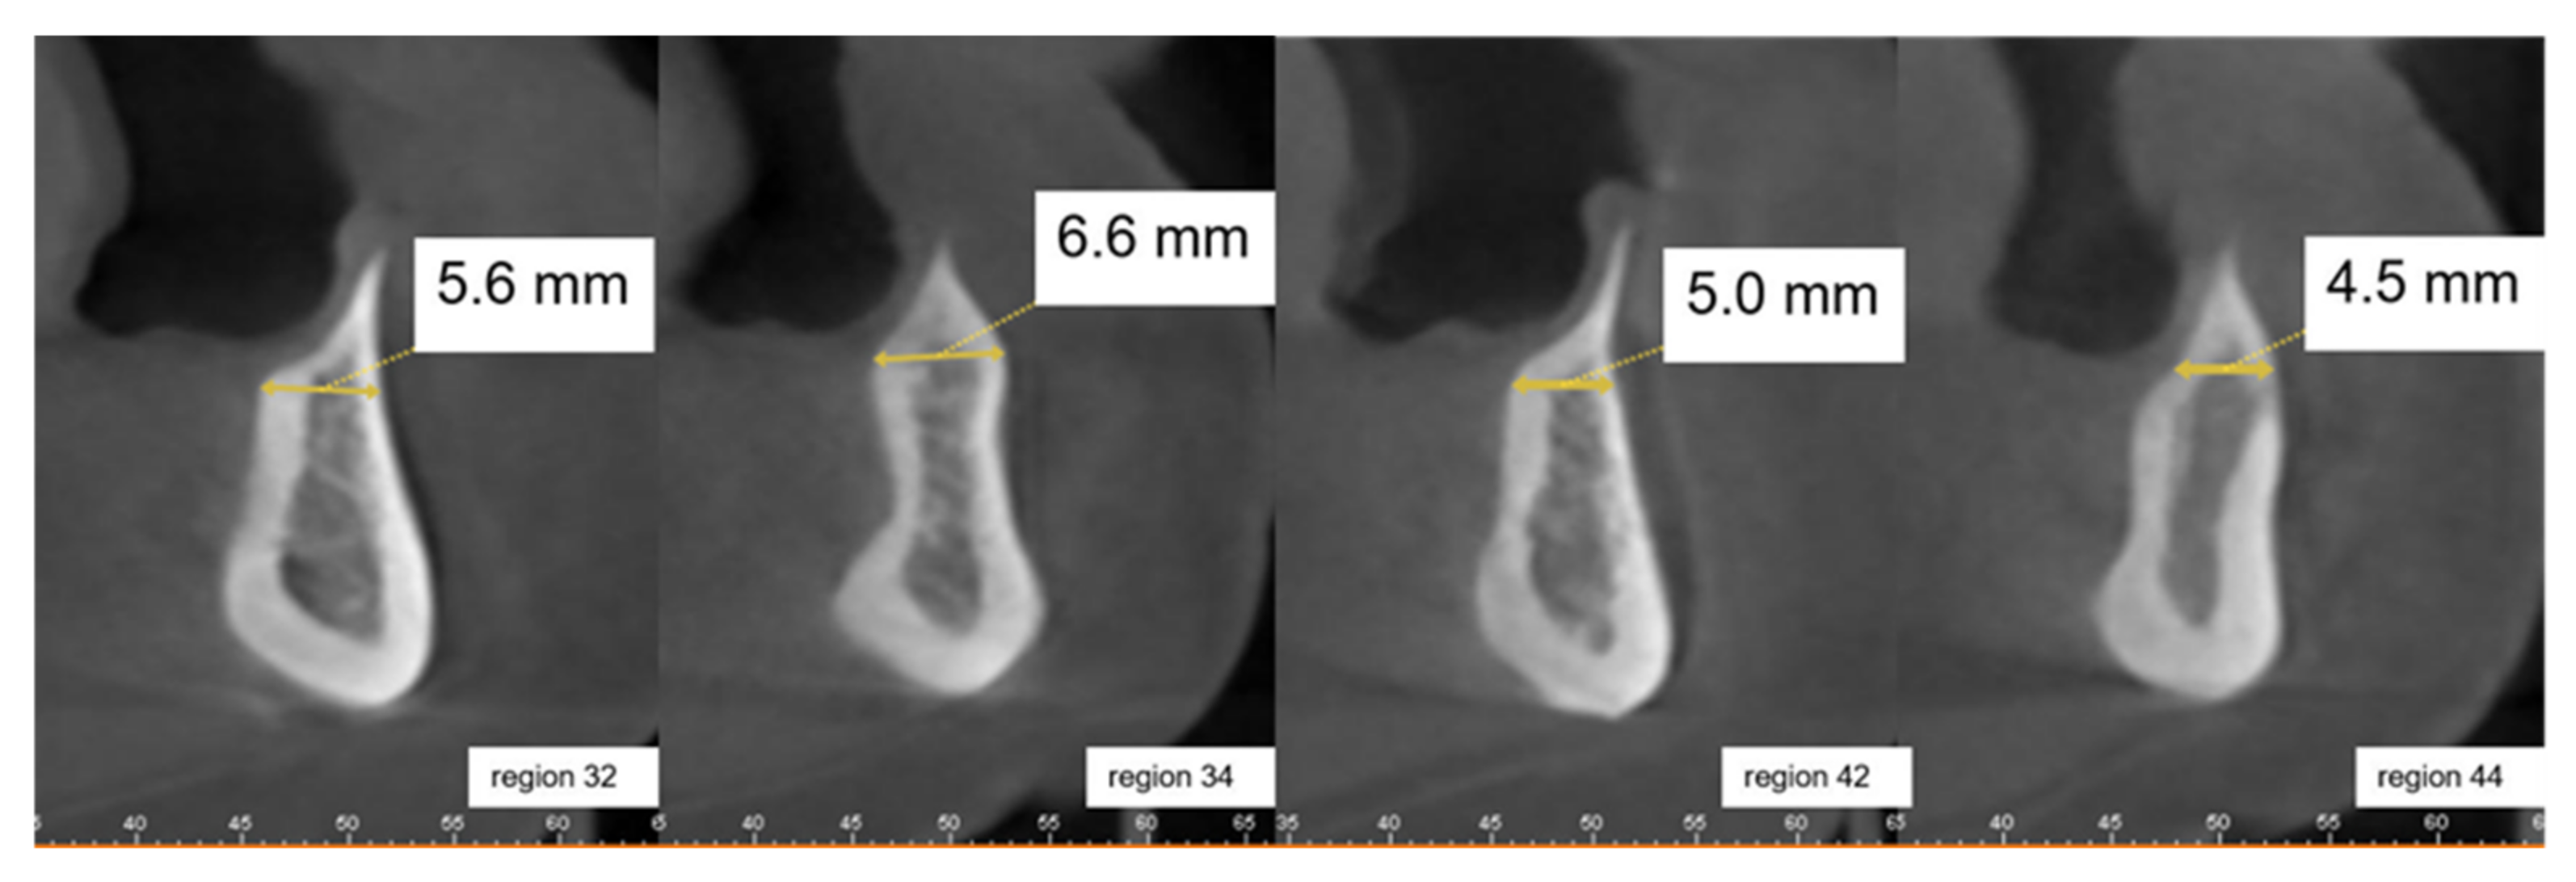

2.2. Clinical Case Vignettes

2.4. Description of the Clinical Case Vignettes